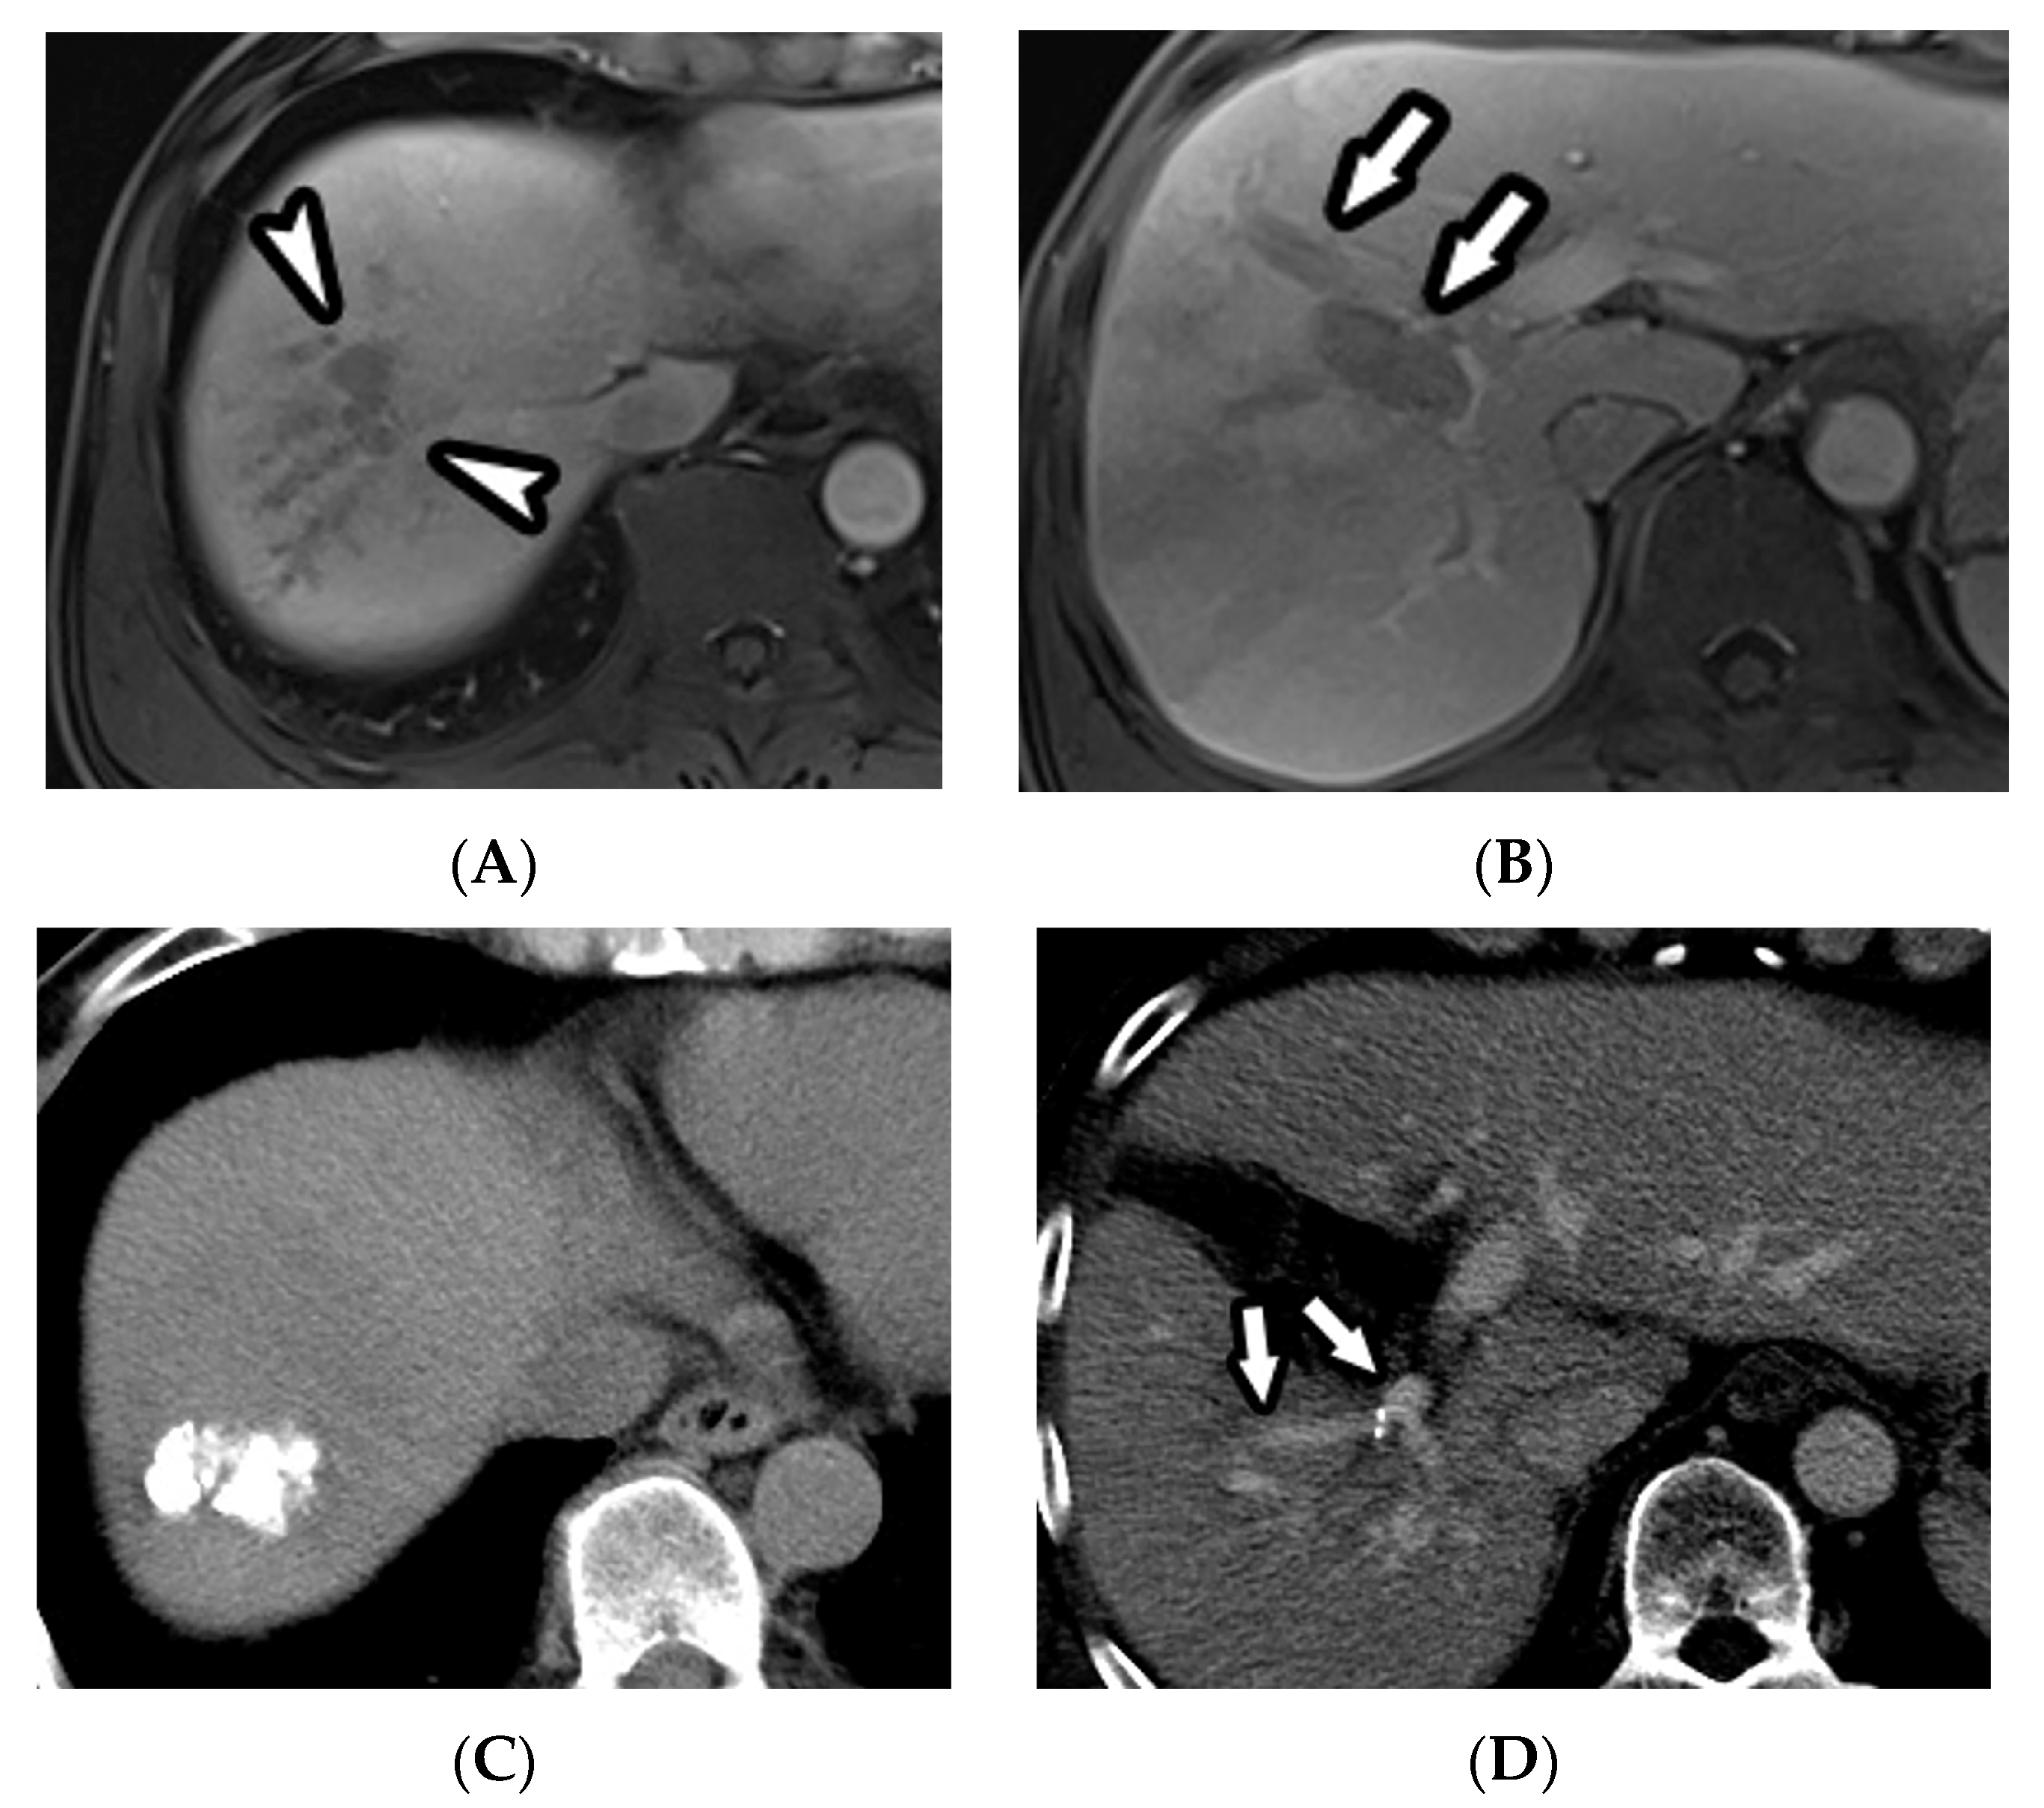

3.2. Radiologic Response after Treatment

3.3. Progression-Free Survival Analyses